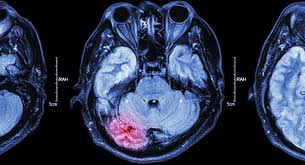

오늘은 뇌졸중 초기증상에 대해서 알아보기로 합니다.

뇌출혈, 뇌경색, 뇌졸중 등 무서운 질환으로부터 건강한 뇌를 지켜내는 것이 건강의 지름길이 아닐까 하는 생각이 듭니다.